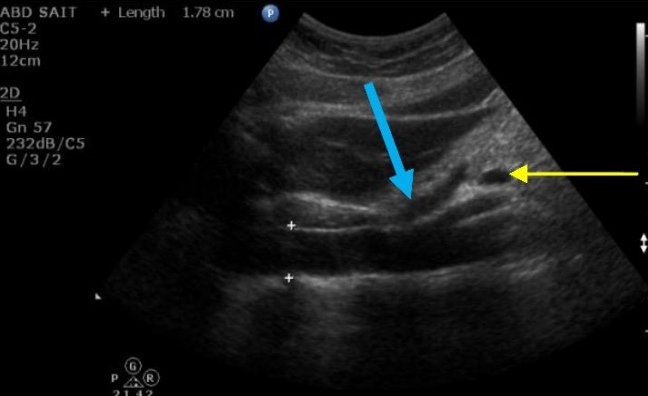

4

Q

Label the Red and blue arrows

A

Red: Body of pancreas

Blue: GE junction